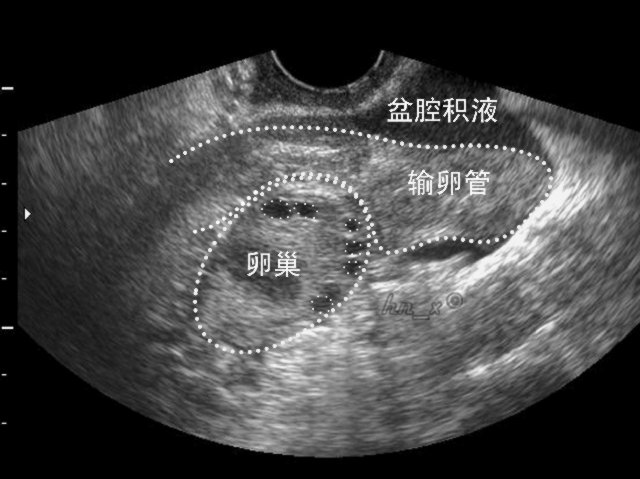

而当积液侵犯到输卵管、卵巢或其他器官时,可导致一系列妇科疾病,因此需要受到足够重视。